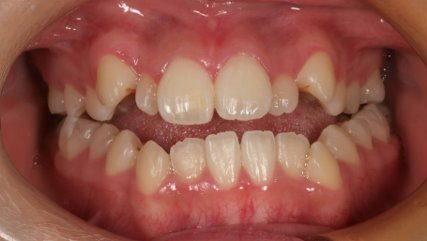

でこぼこがある状態になります。乱ぐい歯とも言われます。見た目がよくない審美障害が主な問題点ですが、その他にもでこぼこが多いことで、歯ブラシによる清掃性が悪くなり、結果、虫歯や歯周病のリスクも上がってしまいます。治療期間が短く済むことも多い為、気になった段階で早期に相談された方が良いと思います。

治療前

治療終了前